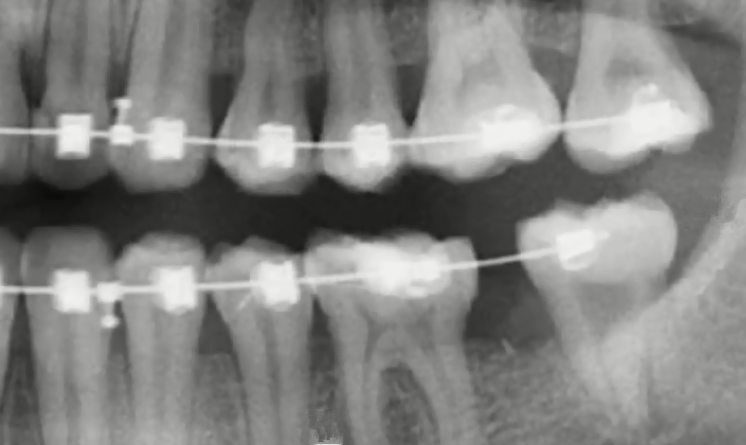

智齒和鄰牙都拔除了

一般來說,智齒把鄰牙齲壞後比較常見的是這樣的幾種處理方法。但是這隻是參考建議,具體(ti) 還要醫生把關(guan) 確診才行。